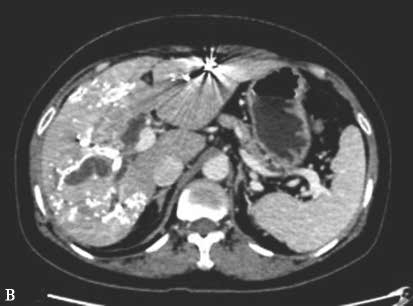

图2-5-1 采用不同栓塞材料实施PVE

B、b.氰基丙烯酸正丁酯栓塞门静脉右支和Ⅳ段支;

A.PVE术前CT;a.PVE术前三维可视化重建;

B.门静脉右支行弹簧微钢圈联合NCBA栓塞,术后2周复查CT见弹簧微钢圈移位至肝左外叶门静脉末梢支,肝左内叶见NCBA分布;b.PVE术后三维可视化重建,NCBA自门静脉右支移位至门静脉左内叶分支。